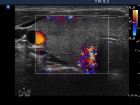

Follow-up examinations (rows from 1st to 8th):

Corresponding sonographic images (row)

2. Note the relation between volume, echogenicity, vascularization and hormone levels.